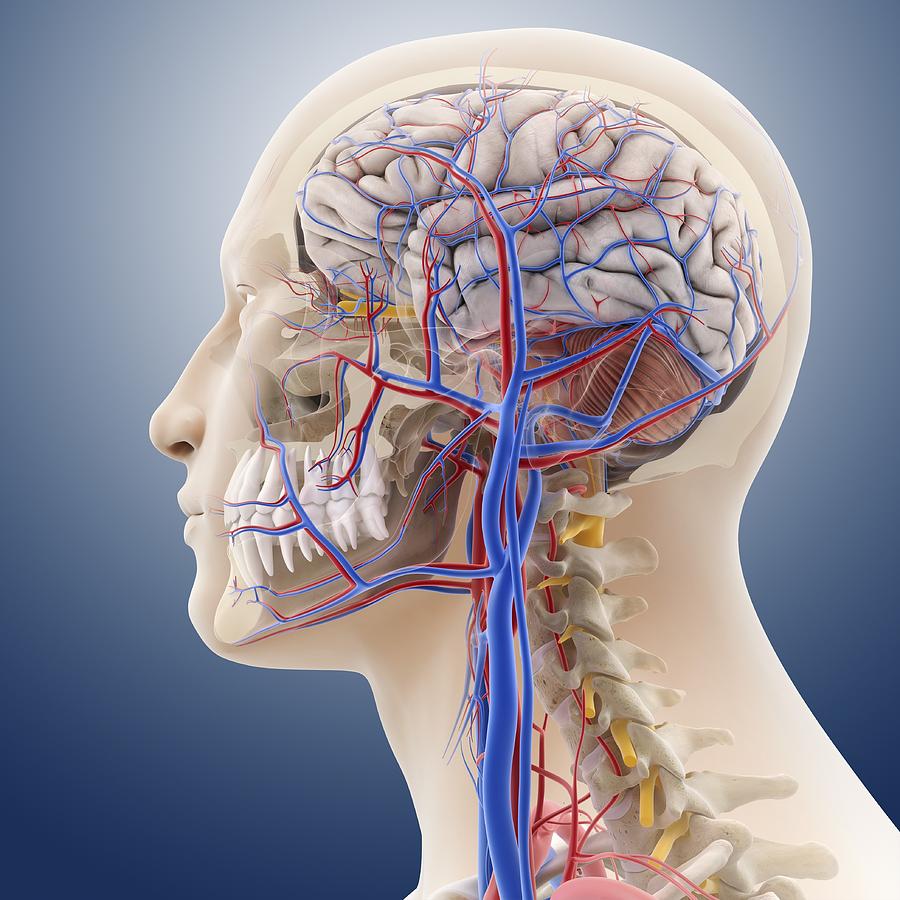

Head Neck anatomy: chapters 6-7 vascular system and glandular tissue. 80 terms. karatwiner. Preview. CDA 104 Instrument ID Ch. 34,35. 39 terms. - is an amalgamation of components of all of the systems of the body - head and neck region is connected to other regions - internally there is the brain - inferiorly there is the thorax - laterally.

Understanding the Head & Neck Scientific Publishing

The gross anatomy of the head and neck lecture 3